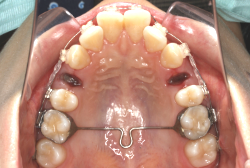

混合歯列期から治療開始した側方拡大による非抜歯症例

「配列の凸凹を治したい」という主訴で来院したケースです。診断の結果、永久歯がすべて生えそろうと、かなり厳しい叢生(歯並びの凸凹のことです)になる可能性が高いと判明しました。原因としては特に上の顎の骨が小さいため、歯を収容する容量不足になっていると診断しました。このケースの場合は、成長発育期に治療開始しますので、顎の骨を土台ごと大きくすることが可能です。

そこで、まず急速拡大装置を使用して上顎骨の拡大を行い、上顎骨の容量が拡大したことを確認後、マルチブラケット装置を使って全体の修正をする、と言う二段階の作戦をとることになりました。

この時期に使う急速拡大装置は、適切な診断に基づいて正しく使用することで確実に骨を大きくすることができます。拡大することで隙間が確保できるので、永久歯の抜歯を避けることができます。

急速拡大装置を1日1回装置の中央にある拡大ネジを、ご自身で回して頂くことで25日間くらいかけて、6mmほど拡大しました。拡大後は、上顎の前歯の隙間が広がっていることがお分かりいただけると思うのですが、土台の骨ごと広がるのでこのような隙間ができます。その後1年半くらいマルチブラケット装置を使用して、全体の修正を行いました。

結局、歯の本数を減らすことなく、すべてご自分の歯を残して正しい配列にすることができました。このケースの場合、2009年10月より拡大と経過観察を行い、2012年3月より1年2ヶ月マルチブラケット装置を装着、2013年5月に治療を終了しました。2段階で行う治療としては短期間で終了しているケースと思います。